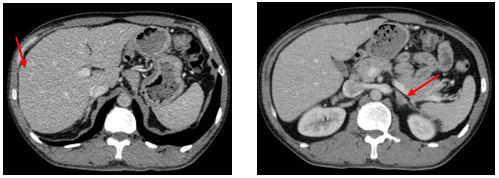

-         CT ổ bụng:

Hình 3. Trên phim chụp CT ổ bụng: Nhu mô gan sát bao gan phân thùy S5 có nốt giảm tỷ trọng trước tiêm, ngấm thuốc kém sau tiêm, đường kính 10mm – Theo dõi tổn thương thứ phát. Dày tuyến thượng thận trái.

Trên phim chụp cắt lớp vi tính ổ bụng:

Trước điều trị:

Sau 3 tháng điều trị: Tổn thương gan và thượng thận đã biến mất.

Hiện tại trong quá trình theo dõi gan và thượng thận 2 bên vẫn chưa xuất hiện tổn thương mới.